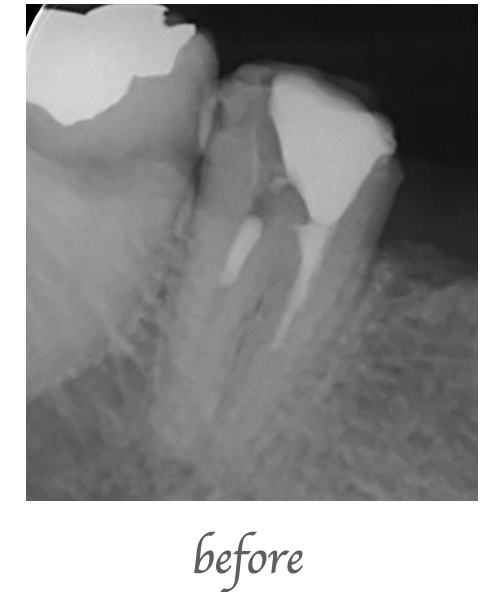

歯が痛いとのことで来院されました。歯を確認すると歯が縦に破折しており、保存不可と判断し抜歯となりました。抜歯後はインプラント治療を希望したため、抜歯即時埋入手術を行いました。

抜歯即時インプラント埋入は、歯を抜いてからインプラント埋入まで一度の手術で治療出来ます。手術後は、約4ヶ月の待機期間をおいて上部構造(クラウン)を作成します。

インプラント治療 ¥480,000(税込528,000)

手術後にかなり軽微ではありますが腫れ、痛み、出血を伴います。感染のリスク、インプラント脱落のリスクがあります。